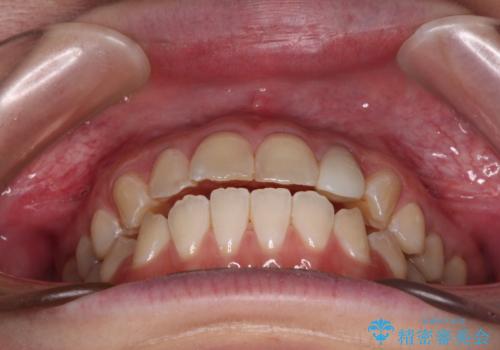

開咬を治す インビザラインによる矯正治療

- 3年4ヶ月

途中1年8ヶ月ほど来院されず、久しぶりの来院後は治療が面倒とのことで、前歯の叢生や隙間に不十分な点が残った状態での終了となりました。